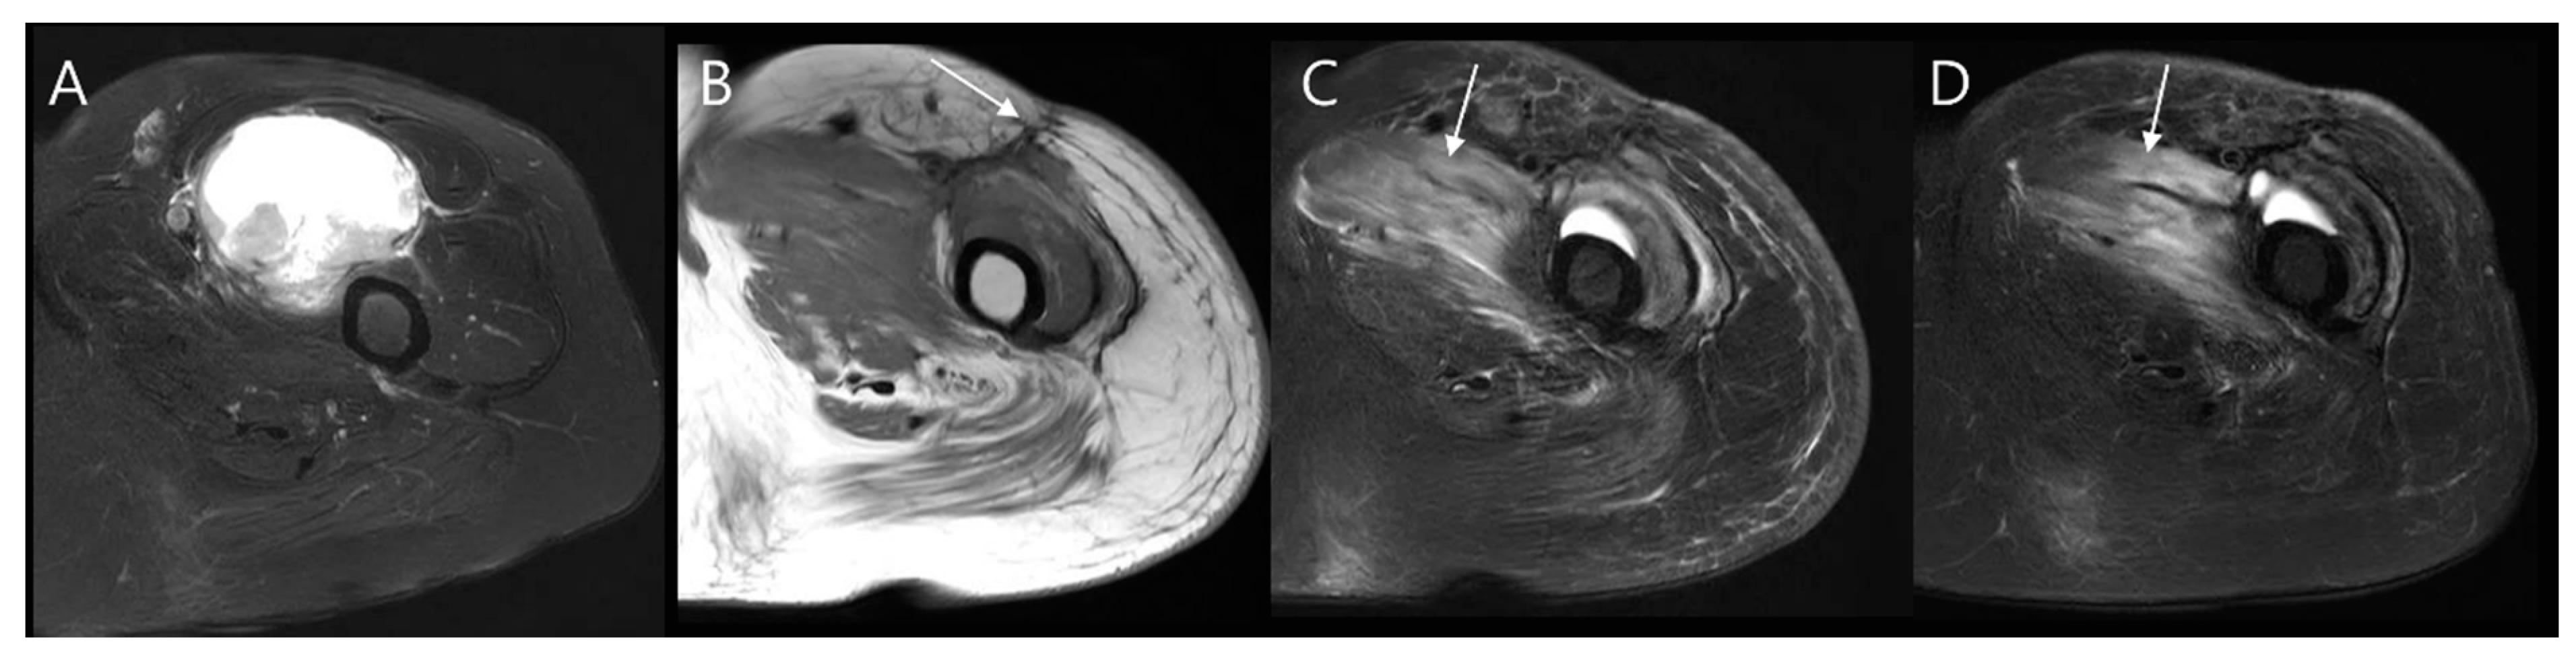

- Noebauer-Huhmann, I.M.; Chaudhary, S.R.; Papakonstantinou, O.; Panotopoulos, J.; Weber, M.A.; Lalam, R.K.; Albtoush, O.M.; Fueger, B.J.; Szomolanyi, P.; Grieser, T.; et al. Soft Tissue Sarcoma Follow-up Imaging: Strategies to Distinguish Post-treatment Changes from Recurrence. Semin. Musculoskelet. Radiol. 2020, 24, 627–644. [Google Scholar] [CrossRef]

- Shapeero, L.G.; De Visschere, P.J.; Verstraete, K.L.; Poffyn, B.; Forsyth, R.; Sys, G.; Uyttendaele, D. Post-treatment complications of soft tissue tumours. Eur. J. Radiol. 2009, 69, 209–221. [Google Scholar] [CrossRef] [PubMed]

- Song, E.H.; Lee, S.Y.; Lee, S.; Jung, J.Y.; Shin, S.H.; Chung, Y.G.; Jung, C.K. Diagnosis of Local Recurrence of Malignant Soft Tissue Tumors after Reconstructive Surgery on MRI. J. Clin. Med. 2023, 12, 4369. [Google Scholar] [CrossRef]